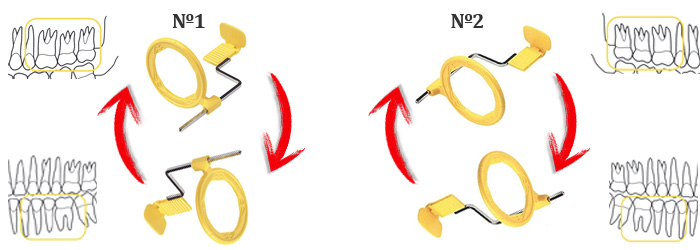

Il existe deux configurations qui permettent la prise de vue de quatre hémiarcades, en inversant simplemnt la position de la plaque :

- Image nº1: Assemblage du XCP pour réaliser la radiographie maxilaire superieur droite (Premier Quadrant), il suffit de le retourner pour la mâchoire gauche (Troisième Quadrant)

- Image nº2: Assemblage du XCP pour réaliser la radiographie maxilaire superieur gauche (Second Quadrant), il suffit de le retourner pour la mâchoire droite (Quatrième Quadrant)